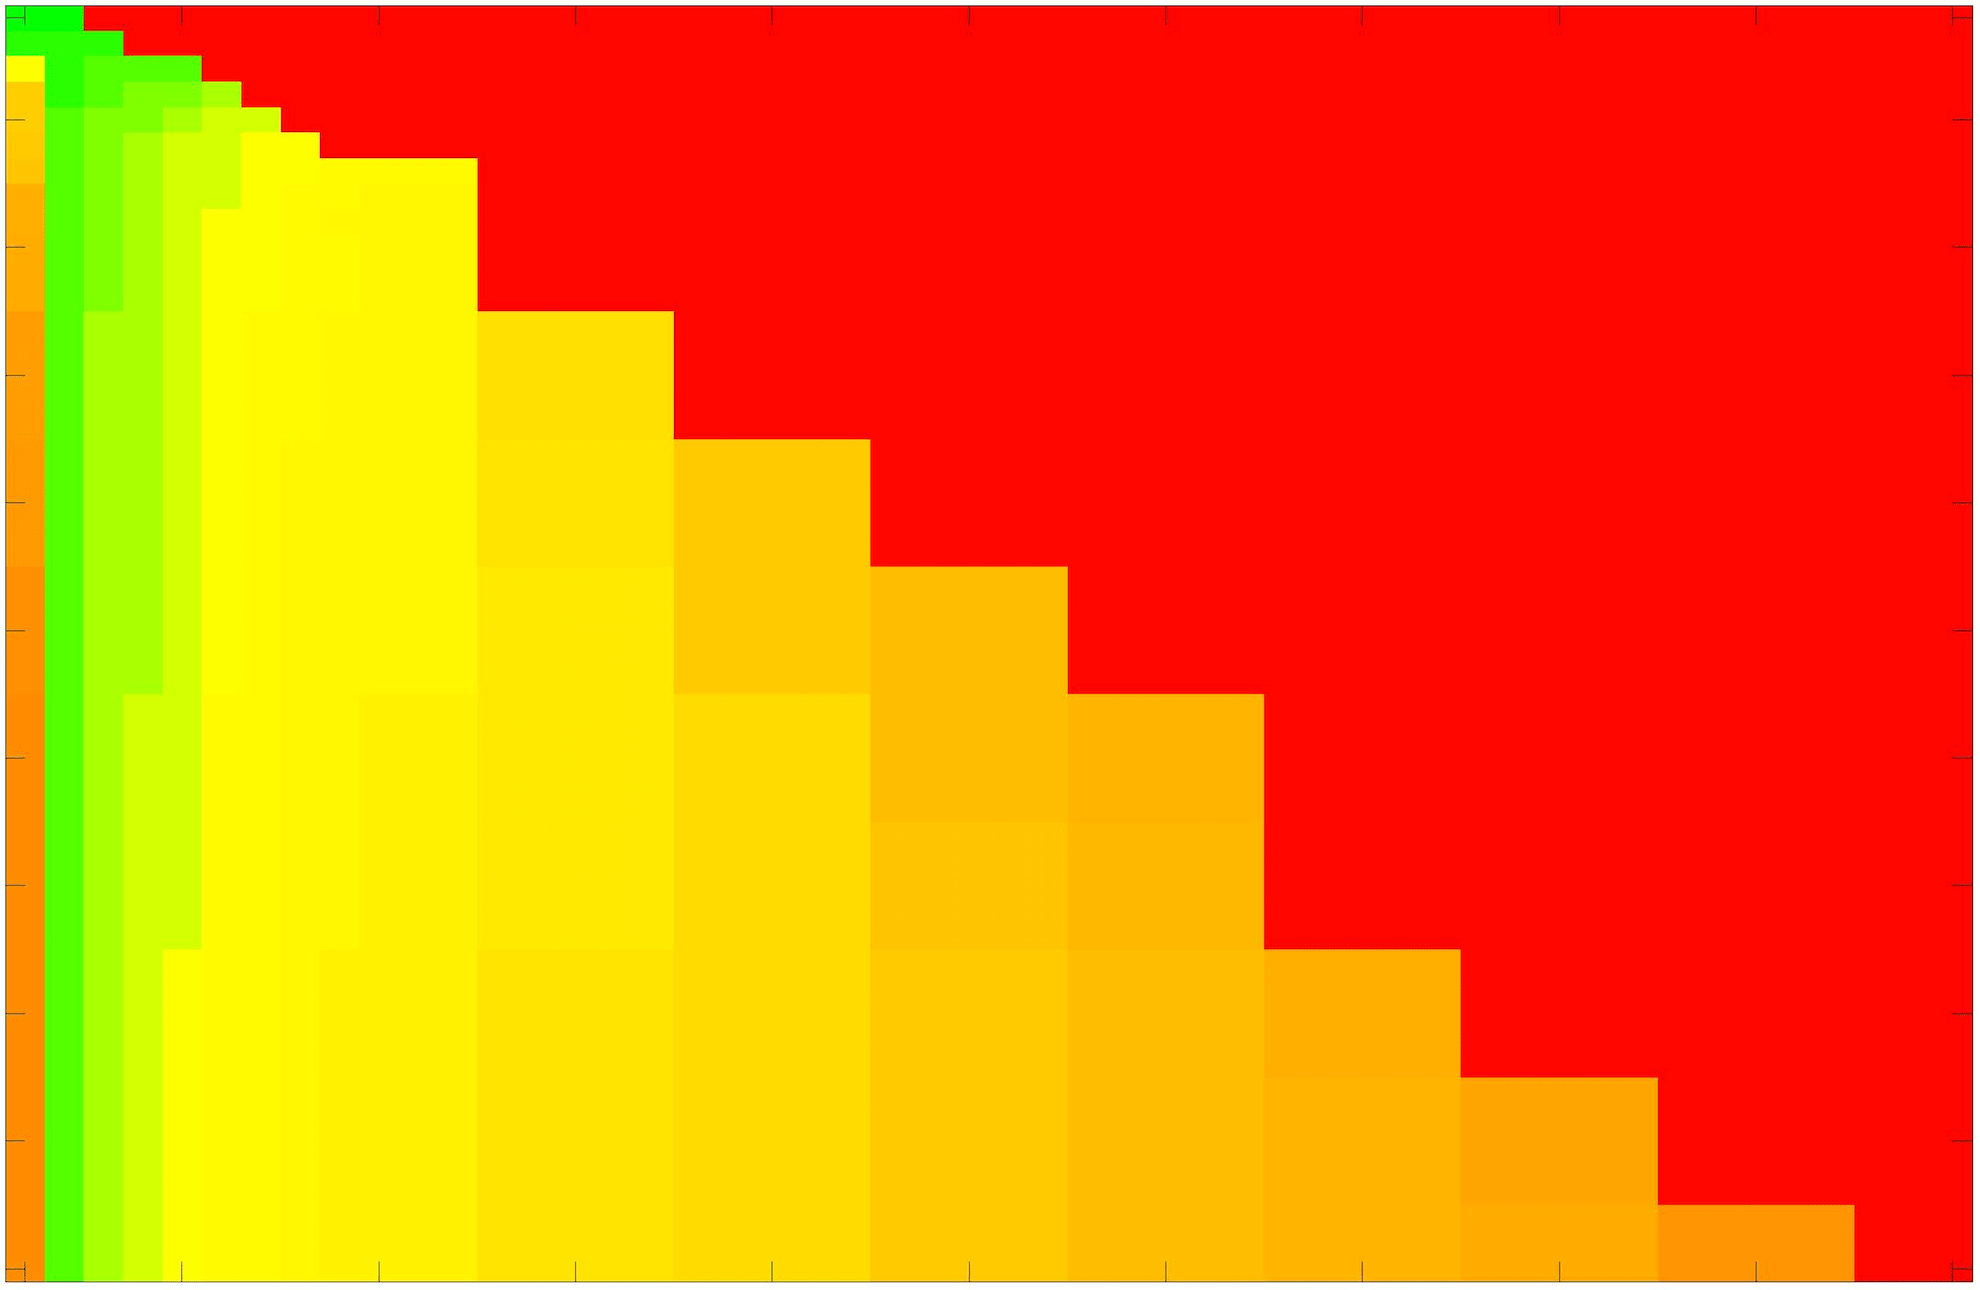

where refers to the number of points in the enclosed region. This takes values in the range , with higher TC values indicating a more accurate segmentation. In the following we will represent accuracy visually from red () to green (), with the intermediate scaling of colours used shown in Fig. 8. This will be particularly relevant in §7.2.

The TC values for the parameter sets are presented as heatmaps in Figs. 11–13. A heatmap is a convenient way to display accuracy results for hundreds of tests concisely. In Fig. 9 we give an example heatmap with the same axes used for those in Figs. 11–13. For each of the combinations of parameter values we give the TC value of the segmentation result and represent it by the appropriate colour. The corresponding colour scale is shown in Fig. 8. Qualitatively, the more green areas of the heatmap the more accurate the model is for a wider set of parameters. Example results for Test Image 5 when varying (with ) for the proposed model are given in Fig. 10. Here it can be seen what each accuracy result corresponds to visually.

Note. The axes have been removed from the heatmaps in Figs. 11–13 for presentational clarity. However, to be explicit, the axes used in all heatmaps are the same as those in Fig. 9.

Synthetic Images. These results are presented in Fig. 11. For Test Images 1–2 we see poor parameter robustness from all competing models, except for GAV which performs reasonably well. However, the proposed model has minimal parameter sensitivity for these images, with good results achieved for almost every combination of values tested. For Test Image 3 all models have a reasonable parameter range (except for RSF), however the proposed model gives better quality results for a wider parameter range. The other models achieve reasonable results here as the foreground intensity of the ground truth is greater than the background , whereas for Test Images 1–2 they are equal . These results highlight the key advantage of the proposed model.

Real Images. In Fig 12 we present results for Test Images 4–6. Here, the proposed model performs in a similar way to its competitors because these images are more typical selective segmentation problems in the sense that there is a clear distinction between the foreground and background intensities. In particular, the values in each case are: Test Image 4 , Test Image 5 , and Test Image 6 . It can be seen that the proposed model is competitive compared to previous approaches. The performance is quite poor for Test Image 5, but is arguably still the best for this challenging case. In Fig. 13 we present results for Test Images 7–9. Here the proposed model outperforms previous approaches significantly for each image. This is mainly due to the type of image considered. Specifically, the true intensities are: Test Image 7 , Test Image 8 , and Test Image 9 . The proposed model is capable of achieving results where , with other models failing completely in these cases.